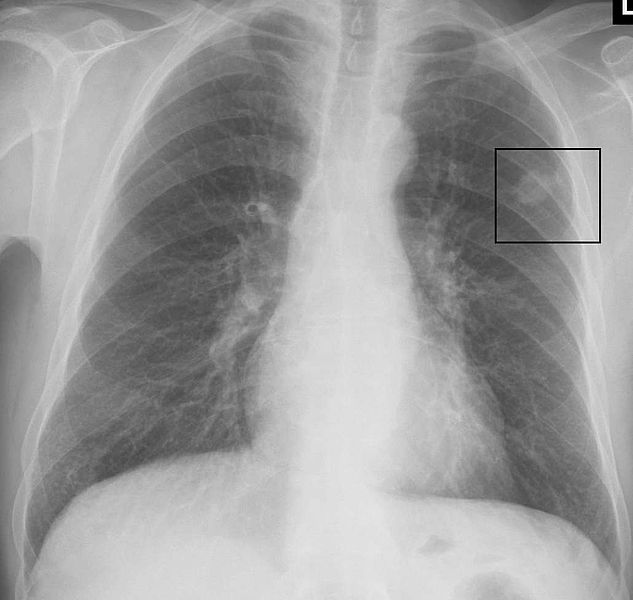

좌상엽에 증가된 동그란 음영(폐암)이 있다. 병변은 대개 주변 폐(검은색)에 비해 하얗다.

만약 공기 주머니가 쪼그라들어 있으면 (숨을 내쉰 상태) 병변과 정상 구조물이 빽빽하게 혼재되고, 병변을 구분하기 힘듭니다. 그런데 공기 주머니가 완전히 팽창 되면 (숨을 들이쉰 상태) 병변과 정상 구조물 간의 구분이 수월해집니다. 의미는 조금 다르지만, 마치 우주 팽창 모델에서 사용하는 풍선과 비슷합니다. 쪼그라든 풍선에서는 아무것도 구분이 안되지요.